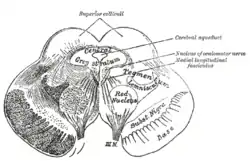

Section through superior colliculus showing path of oculomotor nerve. | |

Transverse section through mid-brain; number 2 indicates the cerebral aqueduct.

Transverse section through mid-brain; number 2 indicates the cerebral aqueduct. Transverse section of mid-brain at level of inferior colliculi.

Transverse section of mid-brain at level of inferior colliculi. Transverse section of mid-brain at level of superior colliculi.

Transverse section of mid-brain at level of superior colliculi. MRI section of mid-brain.